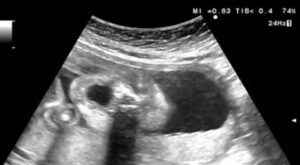

妊娠22週4日のエコー検査の際、画面に映し出された赤ちゃんはあくびをしていました。

エコー中は毎回元気に動き回っていることが多かったのですが、最後に大あくびを見せた赤ちゃんに、先生もママさんも「元気すぎるくらいだね」と笑ってしまったそうです。